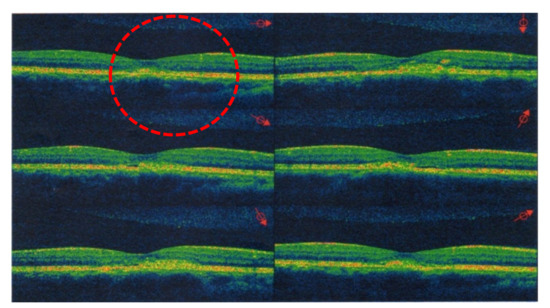

- Tatham, A.; MaCfarlane, A. The use of propranolol to treat central serous choriretinopathy: An evaluation by serial OCT. J. Ocul. Pharmacol. Ther. 2006, 22, 145–149. [Google Scholar] [CrossRef]